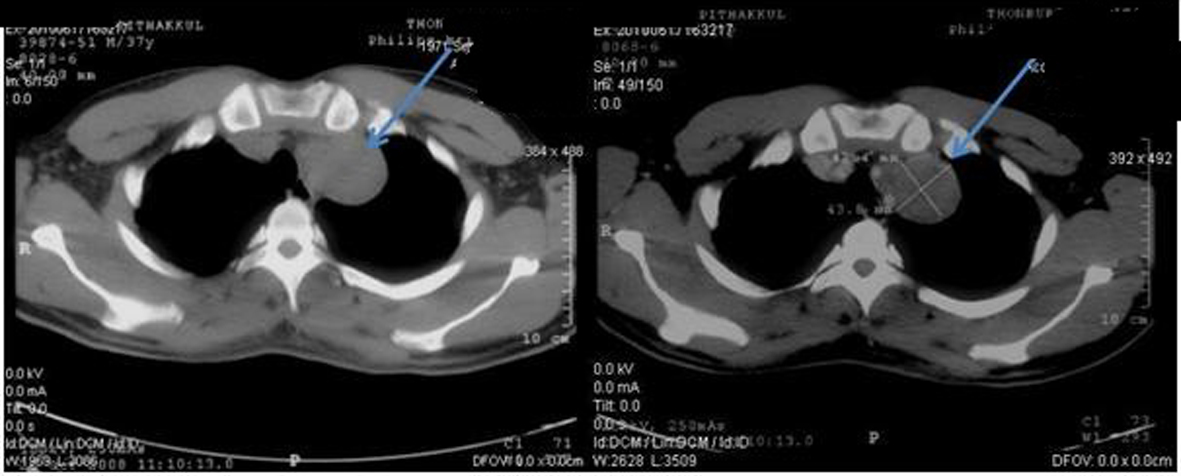

In October 2008, a 37-year-old previously healthy Thai male, with 3cm left supraclavicular lymph node enlargement. The lymph node was biopsied and sent to pathologist and the result showed metastatic well differentiated adenocarcinoma. CT chest and abdomen was done to search for the primary site. It revealed mildly reticular densities at right lung apex, malignant lobulated heterogeneous soft tissue mass at left neck extending downward to level of the aortic arch. Direct tumor invasion was seen at left common carotid and subclavian arteries and left lobe of thyroid gland and partially abuts wall of esophagus. Left paraaortic multi-lobulated nodes were enlarged at the renal level. The mass displaced the left renal vein anteriorly. Some mass effect was noted with mildly dilated left renal pelvis. The 7.4 cm lesion partially abutted wall the aorta and body of the pancreas (Fig. 1-3).Tumor markers including AFP, LDH and CEA were within normal limit.

![]() Click for large image | Figure 1. Pretreatment CT scan of chest in October 2008 (Pre-contrast on left side and post-contrast on right side) showing lobulated heterogeneous soft tissue density lesion at the apex of left lung. |